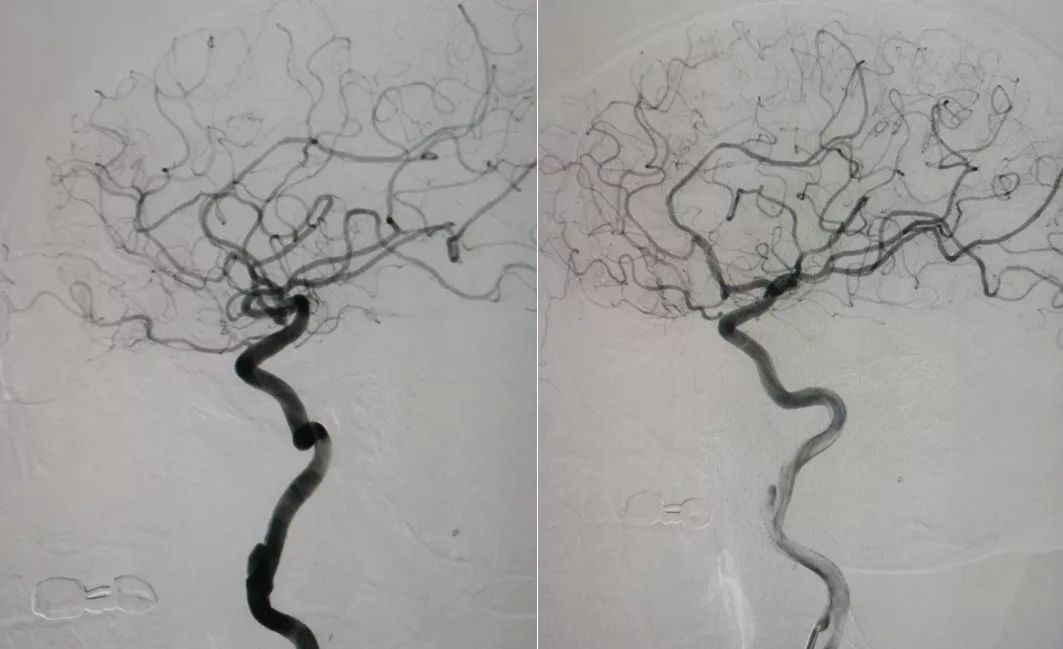

3、术后造影显示Tubridge支架位置良好,动脉晚期瘤内造影剂滞留明显(图6 )。

图6